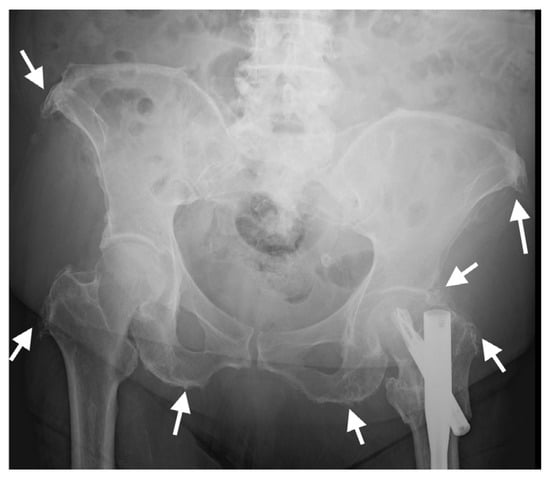

Pelvic and appendicular enthesopathy is common, characteristic extra-spinal manifestation of DISH [72]; consequently, it has been suggested that the spinal involvement threshold be reduced from four to two consecutive vertebrae in the presence of prominent extra-spinal enthesopathy for the classification of DISH [73].

Enthesopathy of the sacrotuberous and iliolumbar pelvic ligaments and insertional enthesopathy of tendons such as the iliopsoas, as seen on pelvic AP radiographs (Figure 8), have been shown to be a good indicator of the presence of radiographic spinal DISH [74,75]. A similar association was described for CT examinations of the pelvis, in which enthesopathy was significantly more prominent in subjects with DISH compared with controls for all entheses evaluated (anterior superior iliac spine (ASIS), pubis, ischial tuberosity, greater trochanter), and enthesopathy at the ASIS and greater trochanter significantly distinguished DISH patients from controls [3].

Figure 8.

AP radiograph of the pelvis of an 82-year-old female with thoracic DISH (not shown). Characteristic whiskering of the anterior superior iliac spine and ischial tuberosities (arrows) is present on both sides, resulting from enthesopathy in these regions.

Pelvic enthesopathy on radiographs in DISH has a distinct appearance, with hypertrophic whiskering of entheseal attachments, whereas in SpA, bone proliferation is milder and is associated with bony erosion and sclerosis [87]. Moreover, while prominent enthesophytes and bone production are seen around the hip joints in DISH, the principal radiographic findings in SpA are concentric joint space narrowing, erosions, and ankylosis, which are uncommon in DISH [87].